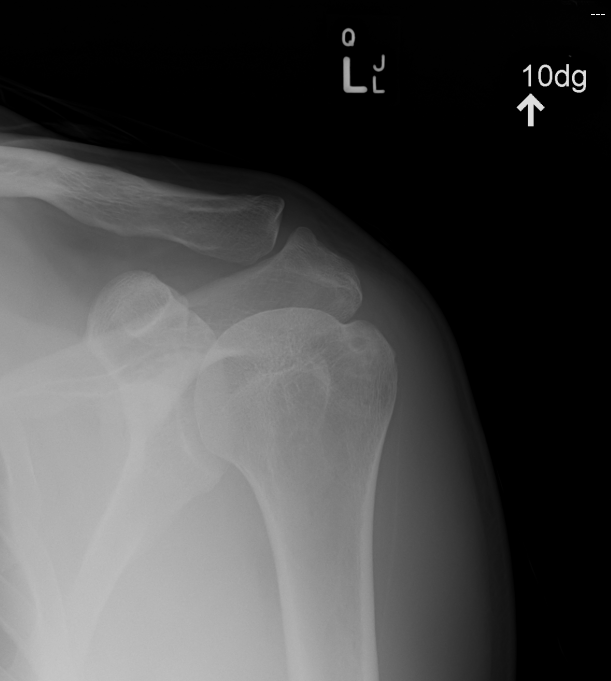

Supraspinatous outlet view

For acromial morphology and impingement

Similar to scapular lateral

- tilt beam caudal 10o